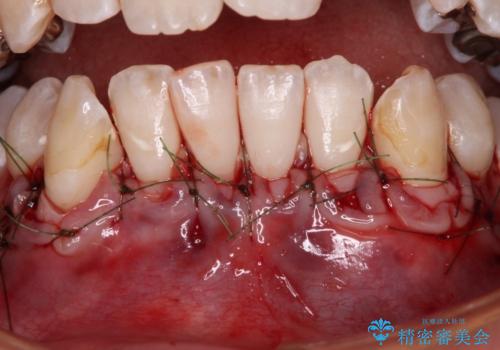

歯肉退縮に対して、上顎からの結合組織移植術(CTG)により、歯根の被覆を行うとともに、歯肉の厚みを増すことで将来の退縮リスクを抑制することとしました。

被覆量が不十分の場合には、追加で手術を行うことで患者様の了解を得ました。

上顎両側から歯肉を採取したたため、術後は痛みや出血で辛い思いをされましたが、1回の処置で満足のいく結果となりました。